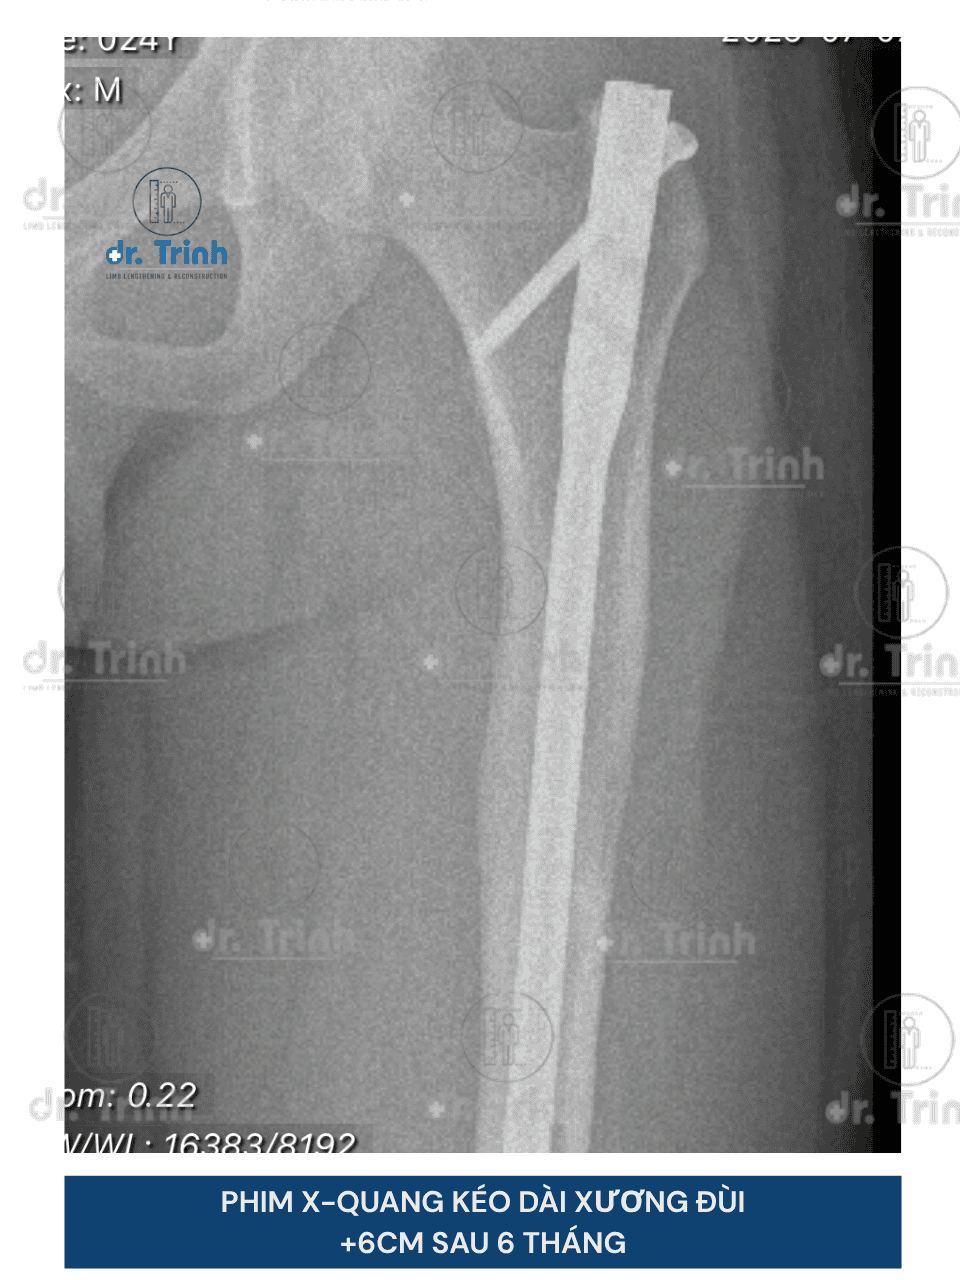

Phẫu thuật kéo dài chân là phương pháp phẫu thuật giúp cải thiện chiều cao giúp cho những người muốn cải thiện chiều cao và vóc dáng. Trong nhiều trường hợp, phẫu thuật kéo dài chân còn giúp điều chỉnh các bất cân xứng chi (chân lệch, chân ngắn bẩm sinh, chênh lệch chiều dài chân sau chấn thương), có thể góp phần mang lại sự cân đối và chức năng vận động tốt hơn.